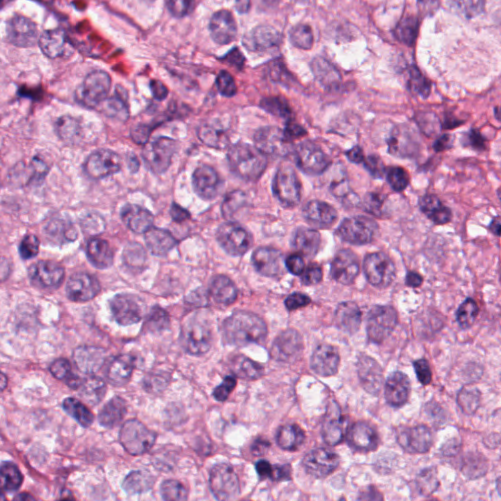

As an essential part of digital pathology, histopathology image analysis is playing increasingly important role in cancer diagnosis, which can provide direct and reliable evidence to diagnose the grade and type of cancer. This paper deals with nuclei segmentation, an important step in histopathological image analysis. The purpose of nuclei semgentation is not only counting the number of nuclei but also obtaining the detailed information of each nucleus. So unlike nuclei detection, here the outputs are the contour of each nucleus instead of only the position of their central points. Hence we can exactly extract each nucleus from the image and make it available for further analysis. For example, the features of the individual nucleus and the distribution of nuclei clusters can be used to grade and classify status of breast cancers [3, 4]. Because of appearance variation such as color, shape, and texture, nuclei segmentation from histopathological images could be very challenging, as illustrated in Fig.1, in which it is very challenging even for human to recognize and segment all nuclei within the images. Fig.1(a) and Fig.1(b) illustrate two histopathological images from different organs. Fig.1(c) and Fig.1(d) are two histopathological images from same organ but have different cancer grade.

H&E stain is the most widely used stain protocol in medical diagnosis. Typically, the nuclei of cells are stained to blue by Haematoxylin while cytoplasm is colored to pink by Eosin. But in practice, the color of H&E stained images could vary a lot due to variation in the H&E reagents, staining process, scanner and the specialist who performs the staining, as shown in Fig.1. A few H&E stain normalization methods[23, 24, 25] have been proposed to eliminate the negative interference caused by color variation. We tried two of them[23, 25] to normalize the raw H&E stained images. For our segmentation algorithm, we did not find any considerable difference between these two normalization methods. Particularly, the result shown in experiment section III is generated based on the images normalized by the method in [23]. Given a target image, this method is able to convert one image’s color into the target image’s color space based on sparse non-negative matrix factorization(NMF). We choose one best stained H&E image as the target and convert other images into its color space. According to the recommendation in [23], the hyper-parameter should be set between 0.01 and 0.1. In our experiment, is set to 0.1.

Figure 6 shows how our method segments the nuclei step by step. The color variety is well controlled by the color normalization procedure. The prediction result shows clear nuclear areas and nucleus boundaries. In the final segmentation result and ground truth image, each nucleus is represented by a different color.